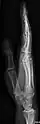

- Fingers - DP and Lateral

- Radius and Ulna - AP and Lateral

- Wrist - DP and Lateral